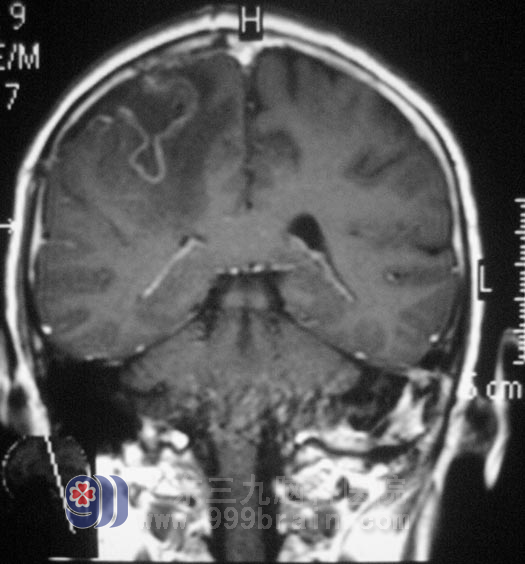

入院时伍女士呈深昏迷状,GCS评分6分,右侧瞳孔直径5mm,对光反射消失,左侧瞳孔直径4mm,对光反射迟钝,头颅MRI结果提示:右侧额叶占位,伴有出血,脑疝。综合神经外科鲁明主任亲自主刀急诊行右侧额叶占位切除术+去骨瓣减压术,见中央前回处黄色透明状病灶,显微镜下予以缜密切除。手术过程顺利,返回监护室予专科监护,双侧瞳孔等大等圆,对光反应灵敏,予抗炎、脱水、营养等对症治疗,术后第三天,伍女士神志清醒,对答切题,四肢活动基本正常。一周时间的治疗后,伍女士已经可以下床自行活动。术后经病理证实为:胶质细胞瘤WHO III级。已转放疗科行后续治疗。http://www.999brain.com/